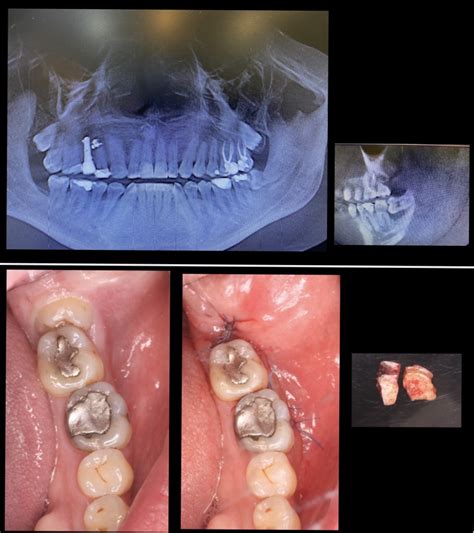

El primer paso en el procedimiento de extracción de un diente, será hacer una radiografía de la pieza que causa los problemas. La extracción dental es un procedimiento quirúrgico que suele realizarse bajo anestesia local.

Procedimiento de Extracción Dental

Tipos de Extracción Dental

- Extracción Dental Simple: Se trata de dientes que están a la vista y es el propio dentista quien lleva a cabo la intervención.

- Extracción Dental Quirúrgica: Es más complicado, ya que en este caso, quizás tengas un diente impactado que ha quedado parcial o totalmente atrapado dentro de la mandíbula o un diente que está ‘fusionado’ al hueso (anquilosado). Es más probable que este procedimiento lo lleve a cabo un cirujano oral especializado, ya que es necesario hacer una incisión en la encía y extraer algo de hueso.